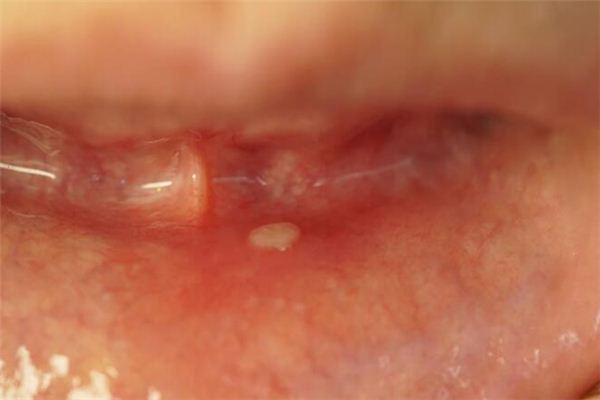

梦见任何物体上的溃烂,都是邪恶之梦。

年轻人梦见溃烂,预示着死亡或同伴的背信弃义。

老年人梦见溃烂,预示着悲伤和孤苦伶仃。

梦见眼睛糜烂,要小心,别只注重眼前利益而最后吃亏。

梦见腐烂的东西,预示要经历风雨,痛苦之后预示着新生。